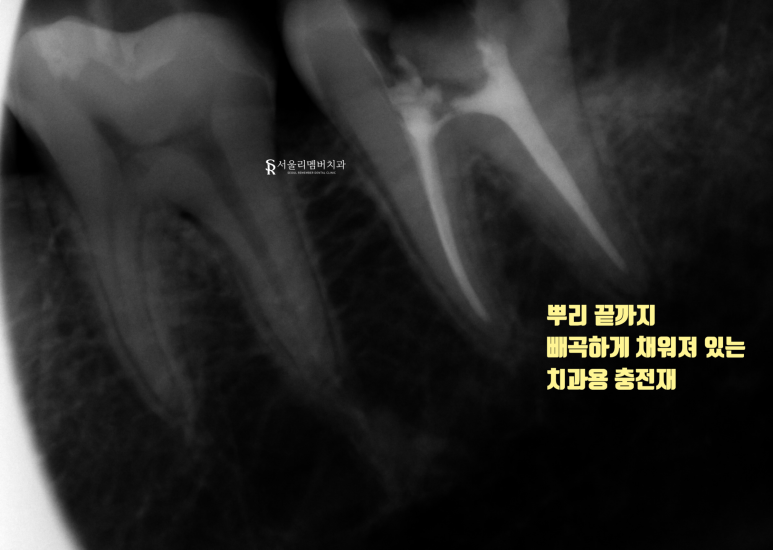

충전재를 사용하여 밀폐를 해주었습니다.

아까 뻥 뚫려 있던 통로는

좀 더 단단한 재료를 사용하여

외부 이물질이나 세균들이 들어가지 않도록 메꿔드렸네요.

자, 이제 최종 보철만 올려드리면 끝이 나는데요.